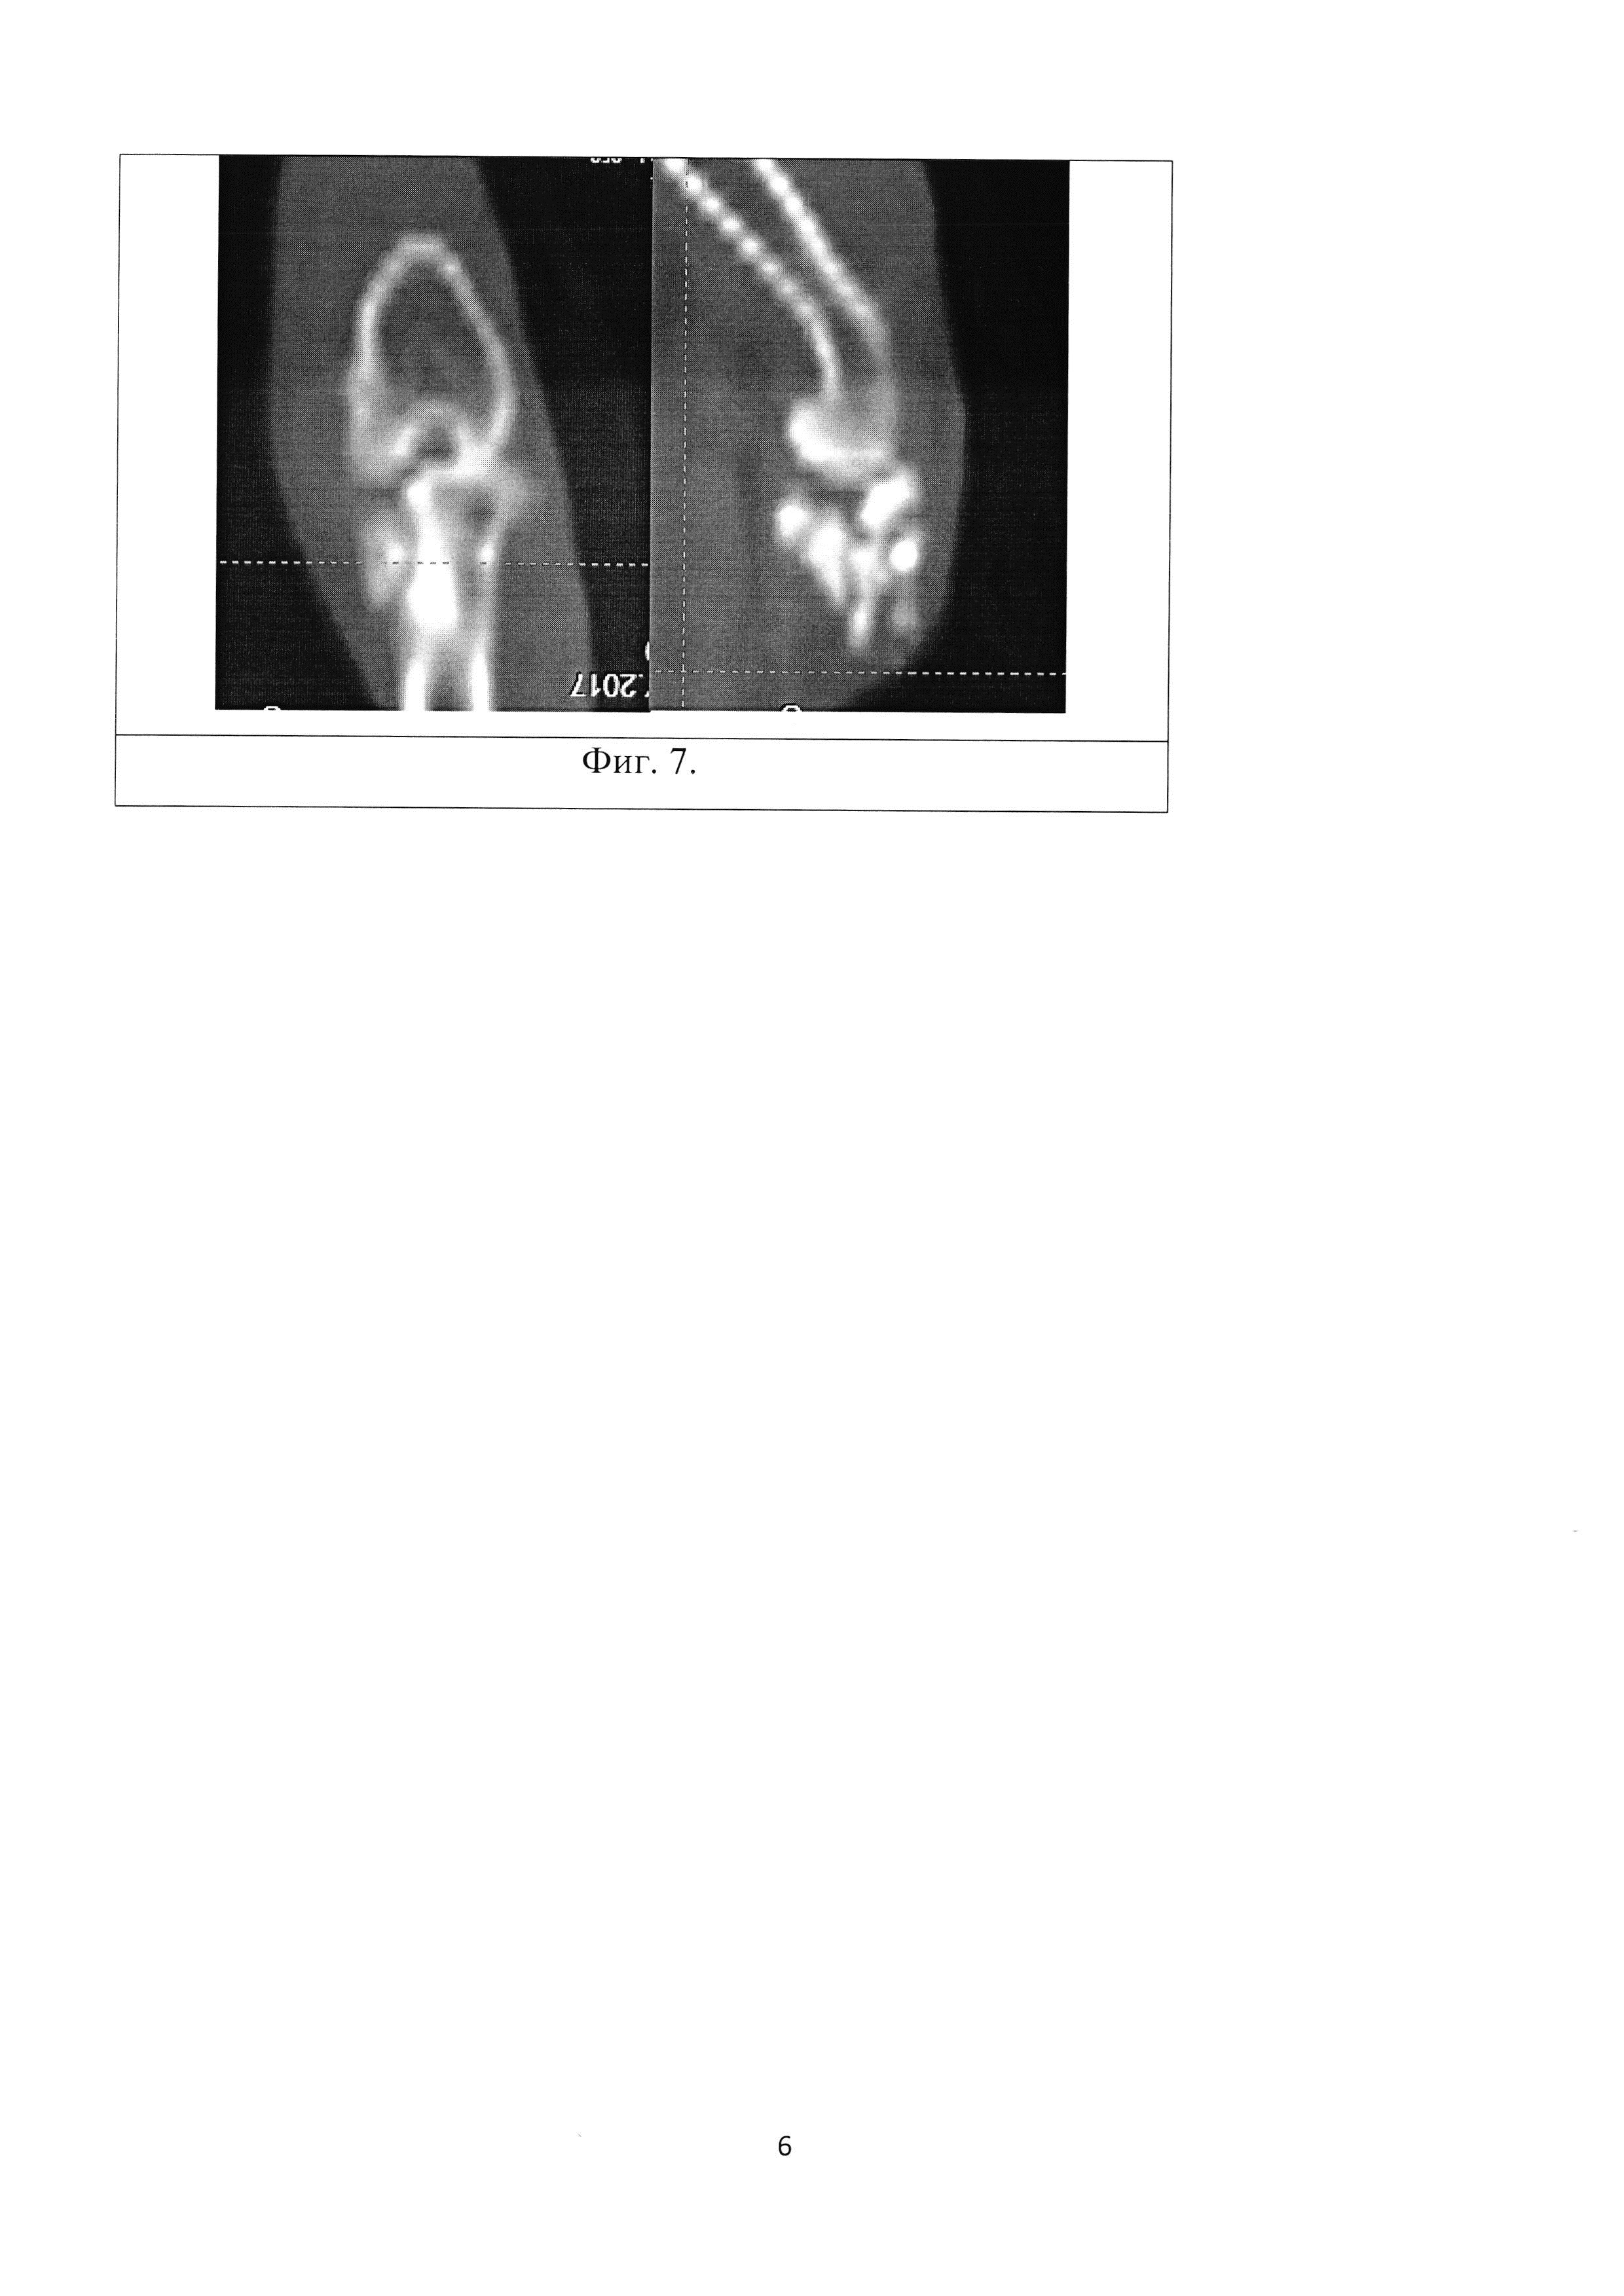

Изобретение относится к экспериментальной медицине, а именно к травматологии и ортопедии, и может быть применимо для изучения пато- и морфогенеза внутрисуставного импрессионного перелома и разработки способов хирургического лечения импресионного перелома эпифиза длинной трубчатой кости. По данным ряда авторов, внутрисуставные переломы в области коленного сустава составляют от 1,5 до 6,9% от всех переломов костей скелета и 10-12,2% от всех внутрисуставных переломов, а переломы мыщелков большеберцовой кости, относящиеся к тяжелым внутрисуставным повреждениям, составляют около 7% от всех переломов опорно- двигательного аппарата. Данный вид повреждений часто сопровождается импрессией костной ткани со стороны суставной поверхности и повреждением важных мягкотканых структур, что следует из особенностей строения сустава (отсутствие значительной мышечной массы, близкое расположение магистральных сосудов, нервов) и сложности его кинематики (Embden D., Stollenwerck G.A., Koster L.A., 2015). Актуальность разработки методов изучения внутрисуставных переломов определяется тем, что для переломов проксимального отдела болыпеберцовой кости характерна высокая частота неблагоприятных функциональных исходов: нередко в отдаленном периоде после травмы развивается деформирующий остеоартроз, контрактуры, нестабильность коленного сустава. Известен способ моделирования субкапитального перелома бедренной кости (Патент G09B 23/28, Способ моделирования субкапитального перелома бедренной кости. Патентообладатель Государственное бюджетное образовательное учреждение высшего профессионального образования Читинская государственная медицинская академия Министерства здравоохранения и социального развития Российской Федерации (RU). Заявка 2490721, Заявл. 2012-02-17, Опубл. 20.08.2013. - 6 с.), при котором обеспечивают равномерное сдавление шейки бедренной кости хирургическим зажимом типа «Москит» до создания субкапитального перелома. Однако данный способ не соответствует картине истинного, так как прикладываемая на кость энергия бранш рабочей поверхности зажима не может точно соответствовать таковой при истинном переломе, по той причине, что истинный перелом предполагает некую осевую перегрузку, возлагаемую на кость. Также данный метод является наиболее травматичным исходя из того, что двустороннее сдавление живой кости может привести к избыточному размозжению костной ткани, а рассечение капсулы тазобедренного сустава может обусловить развитие асептического некроза головки бедренной кости ввиду нарушения ее кровоснабжения. Также следует отметить, что пример субкапитального перелома бедренной кости не соответствует картине импрессионного перелома. Известен способ моделирования несрастающихся переломов длинных трубчатых костей, при котором производят поперечную остеотомию трубчатой кости в ее самом узком месте с помощью пилы Джигли (Патент 2323694, А61В 17/56, Способ моделирования несрастающихся переломов длинных трубчатых костей. Патентообладатель ФГОУ ВПО Белгородская государственная сельскохозяйственная академия. Заявка 2005135524, Заявл. 15.11.2005, Опубл. 10.05.2008. - 6 с.). Однако перелом не соответствует картине истинного ввиду создания его с помощью пилы. Кроме того, данный метод является наиболее травматичным исходя из того, что проволочное витое полотно пилы Джигли обладает слишком большой толщиной (0,5 мм), что может обусловить слишком грубый и избыточный распил кости. Тем самым не отражается этиопатогенез перелома кости. Также следует отметить, что пример субкапитального перелома бедренной кости не соответствует картине импрессионного перелома. Известен способ создания перелома кости в эксперименте, сущность которого состоит в том, что после обезболивания линейным разрезом обнажают поверхность кости на участке предполагаемого перелома (Патент SU 547211, 2 А61В 17/00, Способ создания перелома кости в эксперименте. Патентообладатель Московский городской ордена Трудового Красного Знамени институт скорой помощи им. И.В. Склифосовского. Заявка 1929378/13, Заявл. 28.05.73, Опубл. 25.02.77.). С помощью ножовочного полотна производят надпиливание кортикальной пластинки кости в поперечном направлении в области предполагаемой линии излома. Надпиливание кости производят на глубину кортикального слоя, создавая таким образом зону наименьшей сопротивляемости кости физическим нагрузкам. Захватывают сегмент конечности на протяжении резким ротирующим (при косом расположении линии надпила) или изгибающим (при поперечном надпиле) усилием, производят перелом кости. Однако при данном способе истинный перелом получают только на участке кости на стороне противоположной надпилу, что не соответствует патомеханике травматического перелома. Также данная методика является наиболее травматичной, так как излом кости производиться вручную и сила, прикладываемая к конечности, ничем не контролируема, что может привести к избыточному сгибанию конечности и травме мягких тканей. Нужно сказать, что данный способ моделирования перелома не соответствует картине импрессионного перелома кости. Прототипом данного изобретения стали истинные этиопатогенетические механизмы импрессионного перелома губчатых структур эпифиза любой длинной трубчатой кости. Кортикальная пластинка кости обладает большей, по сравнению с губчатым веществом, площадью цельной поверхности и, следовательно, большей упругостью. Когда на поверхность кортикальной пластинки воздействует определенная однонаправленная сила, запредельная по отношению к трабекулярному веществу, но недостаточная для разрушения компактного, трабекулы губчатого вещества начинают деформироваться и ломаться, а компактное вещество кости начинает заполнять этот объем дефекта, в результате чего образуется импрессионный дефект без четких границ. Технический результат: способ моделирования является высоковоспроизводимым и позволяет приблизить модель к реальному механизму развития патологического процесса. Для создания модели импрессионного внутрисуставного перелома проксимального отдела большеберцовой кости наиболее приближенной к истинной, производится четырехсторонний распил кости (8×7 мм) 1 в области медиального мыщелка большеберцовой кости (Фиг. 1, Фиг. 4) алмазным металлическим отрезным диском (d=10 мм, толщиной = 1,5 мм), отступя 3-5 мм от суставной поверхности дистально. Образовавшийся прямоугольный участок кости извлекается при помощи зажима по типу «москит». Далее производится надлом и смещение части мыщелка 2 (Фиг. 2, Фиг. 5) в дистальном направлении 3 (Фиг. 2, Фиг. 5) в область костного дефекта 1 (Фиг. 2, Фиг. 5), в результате чего образуется импрессионный внутрисуставной перелом медиального мыщелка проксимального отдела большеберцовой кости 4 (Фиг. 3, Фиг. 6, Фиг. 7). Изобретение поясняется иллюстрациями, на которых представлена поэтапная схема проведения внутрисуставного импрессионного перелома. На Фиг. 1. изображен выпиленный прямоугольный участок кости 1 (8×7 мм), который на дальнейших этапах операции будет извлекаться, освобождая под собой вход в костномозговой канал. На Фиг. 2. обозначено направление смещения эпиметафизарного участка с образованием истинного импрессионного дефекта суставной поверхности медиального мыщелка большеберцовой кости, где: 1 - выпиленный прямоугольный участок кости, 2 - часть мыщелка, 3 - направление смещения. На Фиг. 3. изображена готовая модель истинного внутрисуставного импрессионного перелома 4. Фиг. 4. На фотографии виден прямоугольный участок выпиленной кости 1 (8×7 мм), который извлекался, освобождая вход в костномозговой канал. Фиг.5. На фотографии виден смещенный проксимальнее участок медиального мыщелка большеберцовой кости, где: 1 - выпиленный прямоугольный участок кости, 2 - часть мыщелка, 3 - направление смещения. Фиг. 6. На фотографии виден результат операции по моделированию внутрисуставного импрессионного перелома 4, которая окончилась смещением медиального мыщелка большеберцовой кости дистальнее суставной поверхности. Фиг. 7. На фронтальном и сагиттальном КТ-срезе коленного сустава кролика виден результат операции по моделированию внутрисуставного импрессионного перелома 4 медиального мыщелка проксимального отдела большеберцовой кости, имеется область импрессии и дисконгруэнтности суставной поверхности. Способ осуществляют следующим образом. Животное погружают в наркоз и обрабатывают область оперативного вмешательства, выполняют доступ к медиальному мыщелку большеберцовой кости путем острой диссекции мягких тканей с внутренней стороны голени. Мягкие ткани разводятся, в результате чего обеспечивается доступ к участку кости с надкостницей; костным распатором Фарабефа надкостница сдвигается в дистальном направлении. Анатомическим ориентиром для дальнейших действий является общее сухожильное крепление мышц внутренней поверхности бедра - «поверхностная гусиная лапка». Алмазным металлическим отрезным диском (d=10 мм, толщиной = 1,5 мм) производится четырехсторонний распил кости (7×8 мм) 1 в области медиального мыщелка большеберцовой кости (Фиг. 1, Фиг. 4) перед вышеуказанным анатомическим образованием, на глубину кортикальной пластинки кости, без проникновения в полость коленного сустава. Извлекается прямоугольный участок кости. Производится смещение мыщелка 2 (Фиг. 2, Фиг. 5) в дистальном направлении 3 (Фиг. 2, Фиг. 5) в область образовавшегося костного дефекта (Фиг. 2, Фиг. 5) для обеспечения дисконгруэнтности суставной поверхности (Фиг. 3). Рана послойно ушивается. Способ моделирования внутрисуставного импрессионного перелома большеберцовой кости иллюстрируется следующим примером. Пример Для выполнения модели был взят кролик породы «Шиншилла» массой 2600 грамм. При работе с животным соблюдались «Международные рекомендации (этический кодекс) по проведению медико-биологических исследований с использованием животных» (1985). После погружения животного в парентеральный наркоз и традиционной обработки операционного поля был выполнен разрез кожных покровов, тупым и острым способом был осуществлен доступ к медиальному мыщелку большеберцовой кости. После разведения мягких тканей, костным распатором Фарабефа надкостница сдвигалась дистально. Далее алмазным металлическим отрезным диском производился четырехсторонний распил кости перед сухожильным расширением «Гусиная лапка». Участок выпиленной кости извлекался и производилось смещение мыщелка в дистальном направлении в область образовавшегося костного дефекта для обеспечения дисконгруэнтности суставной поверхности. Рана послойно ушивалась. Таким образом, предлагаемый способ моделирования является высоко воспроизводимым и позволяет приблизить модель к реальному механизму развития патологического процесса. В ходе эксперимента была сделана серия снимков на КТ аппарате Toshiba Aquilion 64, пример данного снимка представлен на Фиг. 7.